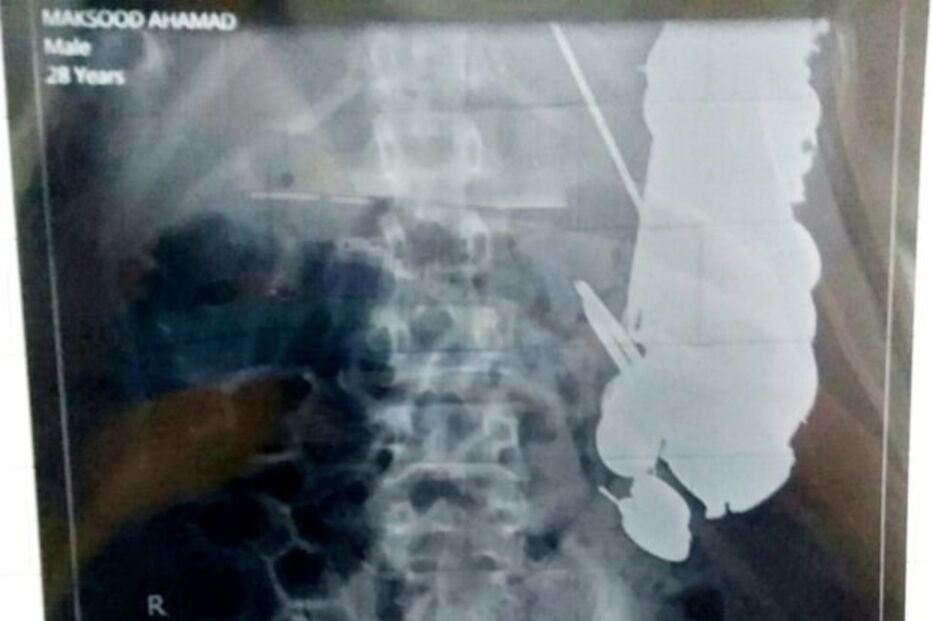

Um homem indiano, de 35 anos, tinha 263 moedas, 100 pregos e dezenas de lâminas de barbear no estômago. Maksud Khan teve de ser operado devido às dores que sentia na zona abdominal, provocadas pelos sete quilos de metal que engoliu.

Segundo a imprensa local, os cirurgiões que operaram Maksud pensavam que o homem estava com uma intoxicação alimentar, e ficaram surpreendidos quando encontraram 7kg de metal no seu estômago. O homem dirigiu-se ao hospital de Satna, em Madhya Pradesh, na India, com dores agudas na zona abdominal.

O médico que liderou a equipa de cirurgia afirmou que o "paciente estava a queixar-se com dores no estômago", e por isso, pensaram em fazer uma endoscopia. "Ficámos chocados quando descobrimos moedas, pregos e porcas no estômago de Maksud", contou Priyank Sharma, médico responsável pela operação, acrescentando que nunca tinha visto nada assim em toda a sua carreira.

Os médicos afirmaram que não existirão danos duradouros nos órgãos internos do homem. "A operação foi feita no momento certo, visto que alguns dos pregos já estavam a perfurar a parede do estômago, causando sangramento", contou um dos cirurgiões.